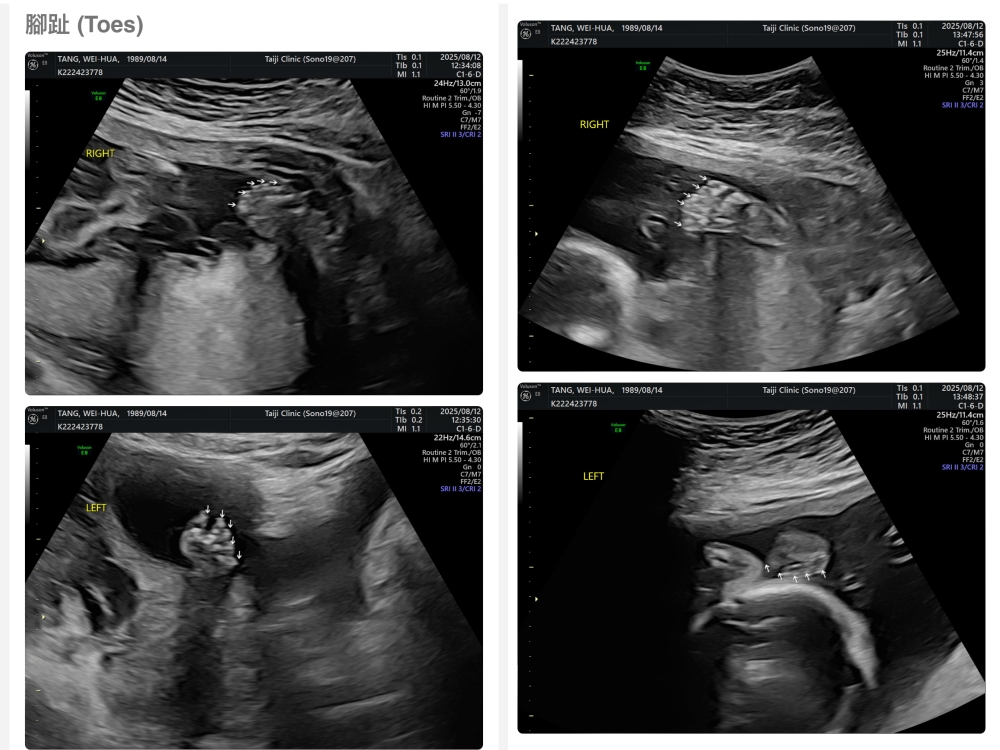

【台兒|高層次超音波|檢查結果】

▲離開診所後會收到MAIL,我們14:05離開,大約是16:45收到mail,裡面會有滿滿的超音波照片,紀錄的很詳細!也會提供紙本的報告,可以給日後產檢的醫師做參考👌